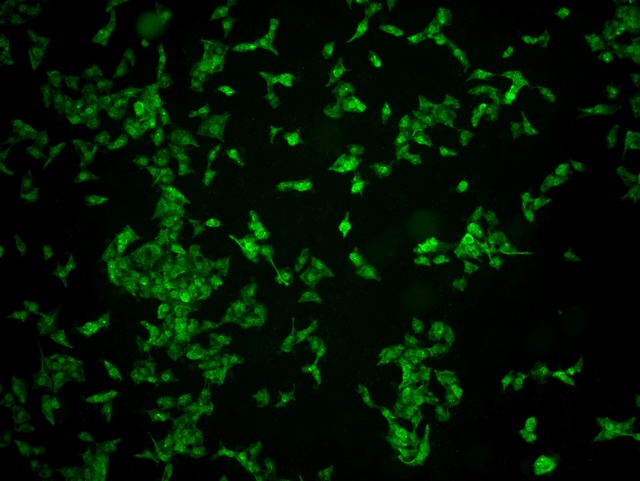

南华大学在生物医学研究领域一直走在学术前沿,近日,该校引进Mshot明美的倒置荧光显微镜MF52-N,搭配显微镜相机MSX2,为细胞切片标本的研究提供了强大的技术支持,进一步提升了科研实力。

MF52-N倒置荧光显微镜以其数显LED荧光模块和深度优化的光路设计,成为细胞切片观察的理想选择。其简单易用的荧光激发操作,大大降低了实验难度,提升了工作效率。同时,该显微镜还能提供高质量的相衬、荧光和明场成像,确保科研人员能够捕捉到细胞切片的每一个细节。

在南华大学的实验室中,科研人员正借助这套先进的显微系统,对细胞切片标本进行深入探索。

此外,MSX2显微镜相机的加入,更是如虎添翼。这款相机以其高分辨率和敏锐的图像捕捉能力,记录了实验过程中的每一个重要瞬间,为数据分析与论文发表提供了有力支持。